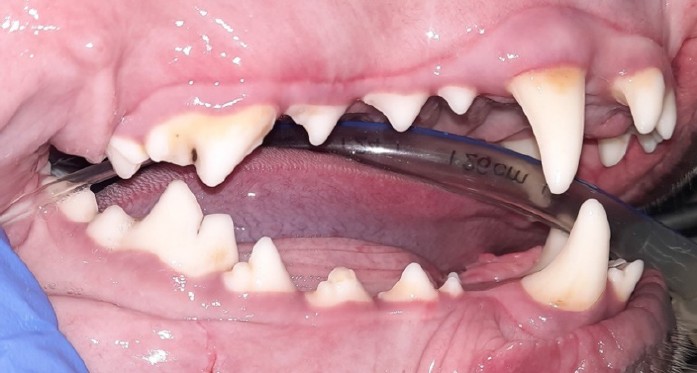

Fig. 6. Dental calculus: a — stage 1 (409 tooth) and stage 3 (404 tooth); б — stage 2 (409–405 teeth); в and г — intraoral radiograph for stage 2 dental calculus.

Source: VTC "Dentalvet".